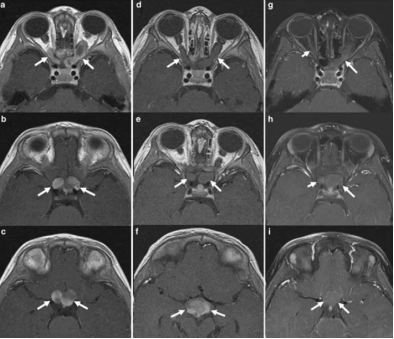

自Dandy进行的提出性工作以来,前视路较前方的肿瘤——视神经胶质瘤的手术切除技术已经很完善。前视路胶质瘤较少见,在眼科患者中的发生率为1/100000~1/10000。切除视神经胶质瘤通常期进...